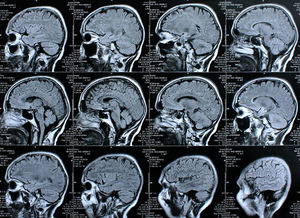

Scan: Computer kann Gedanken lesen (Foto: pixelio.de, Rike) |